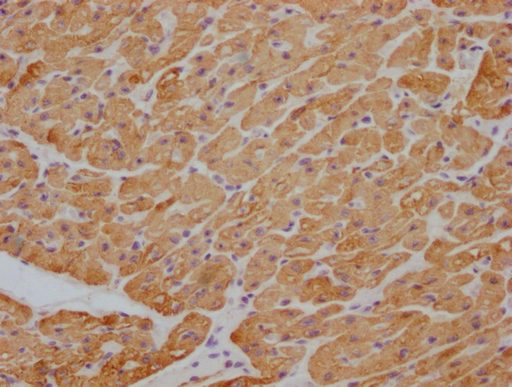

Human heart tissue

1:100